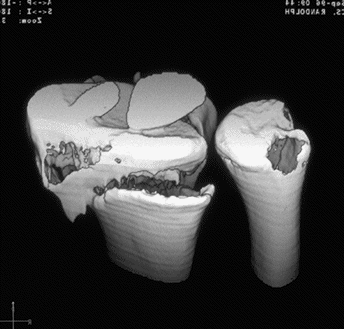

Case 3 CT

Case 4 CT

Case 8 CT